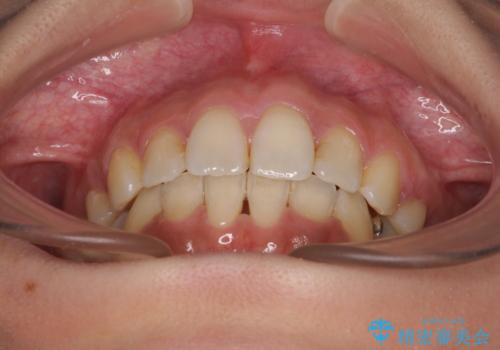

デコボコと口元の突出感 ハーフリンガルでの抜歯矯正

- 前歯のデコボコと上顎の前突感による口の閉じにくさを気にして来院された患者様です。

目立たない装置を希望されたので、上顎が裏側装置のハーフリンガルを選択し、上下左右の小臼歯(計4歯)を抜歯して矯正治療を行うこととしました。

表側のワイヤー矯正に比べると治療期間は長く、費用も高額となりますが、どうしても目立たせたくないという方にはお勧めの抜歯矯正です。